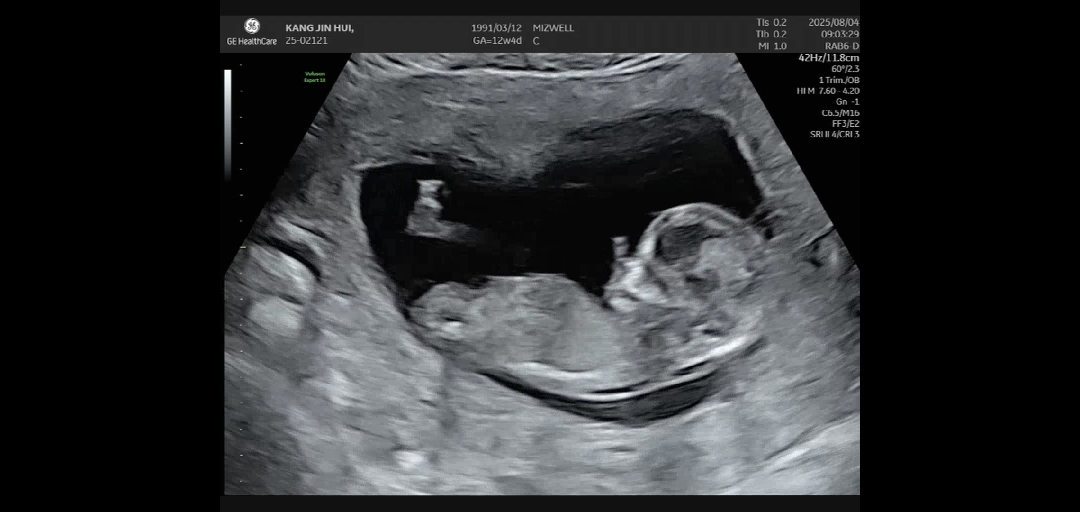

각도법 ! 아들 딸 중 어떤가요?

최대한 옆모습으로 찍은건데 아들일까요? 딸일까요?